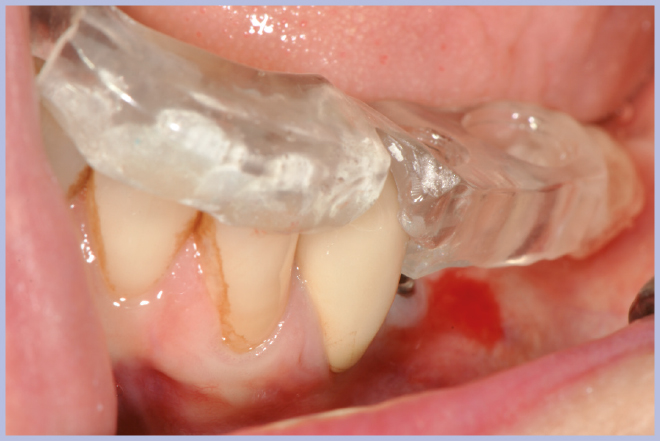

- Figg. 6, 7 – Verifica clinica della stabilità della mascherina radiologica sulla paziente

- Fig. 7

Viene quindi richiesto al tecnico di modificare in laboratorio la mascherina radiologica mediante il posizionamento delle boccole di guida adatte agli impianti da posizionare (Exacone® 6.5 e Exacone® 3,3×8) in asse con gli analoghi del modello Master 3D ed eliminando il repere radiologico standardizzato, trasformandola così nella dima chirurgica (Figg. 14, 15). Si procede quindi alla prova della mascherina sulla paziente per verificarne la stabilità e la corrispondenza esatta con il modello Master 3D (Fig. 16). La seduta chirurgica con tecnica flapless, guida chirurgica e Frese Zero1 dedicate non presenta alcuna difficoltà ; al termine dell’inserimento si posizionano sugli impianti tappi di guarigione bassi per permettere loro di guarire con tecnica sommersa (Figg. 17-27). Si effettua nella stessa seduta una CBCT che dimostra che la posizione clinica degli impianti risulta sovrapponibile a quella progettata dagli Autori (Figg. 28-30).